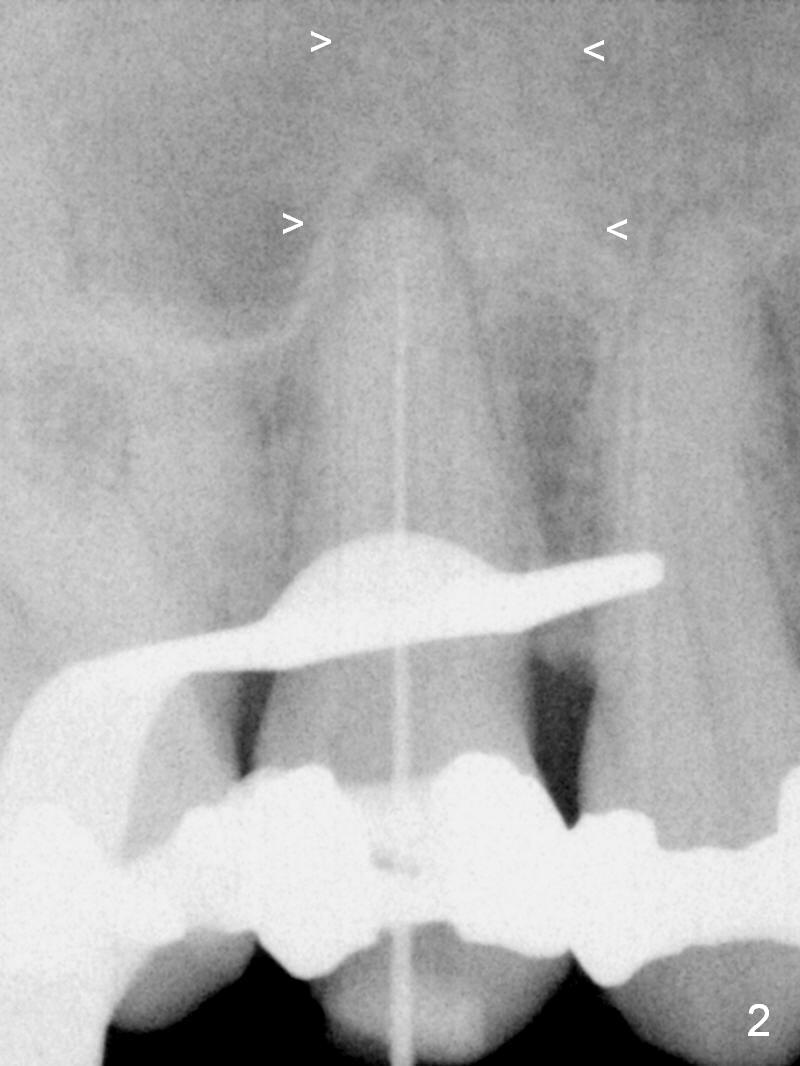

A 55-year-old man had 2nd caries with pulpitis at the tooth #4 a year ago (Fig.1), requiring RCT (Fig.2). The tooth fractured biting on a piece of nut shell inside a moon cake recently (Fig.3 *, 5, 6). There is a sinus septum apical to the apex of the affected tooth (Fig.1-3 arrowheads). After extraction and Metronidazole socket treatment, an immediate implant can be inserted into the septum for primary stability (Fig.4). The diameter of the implant will be decided by the measurement of the mesiodistal width of the root. Magic Expander (ME 3.0 mm) will be used to initiate osteotomy by going deep 4 mm, followed by ME 3.3 mm). If there is resistance to the 1st ME, use 1.6 mm drill. Allograft will be pushed upward with ME 3.3 mm prior to implant placement. Or try to insert (without tapping) ME 4.8 mm as deep as possible, hopefully with stability, and take PA. Place a larger implant for primary stability (4.5x11 mm).